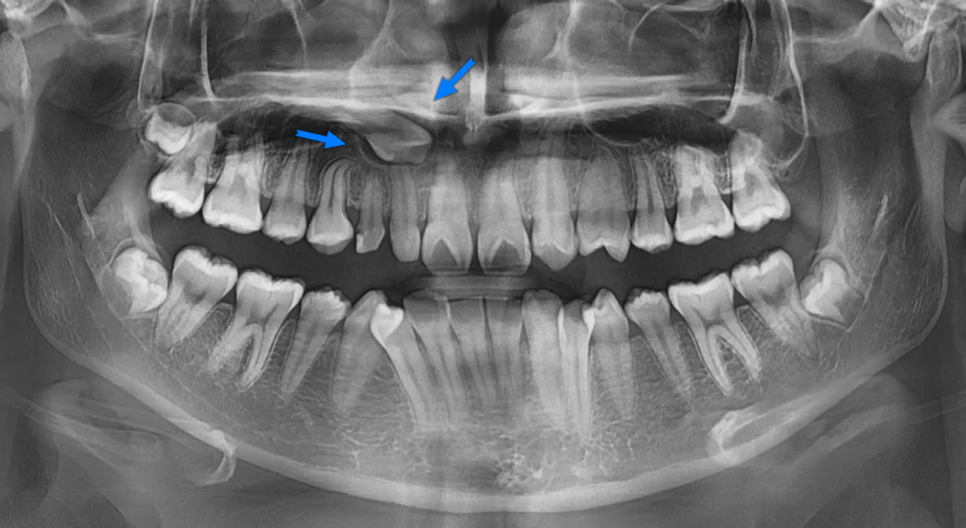

첫번째로 가장 눈에 띄는 것은 사이즈가 유난히 작은 치아들이 존재하는 것입니다. 아래 그림에서 붉은색 화살표는 초등학교때 빠졌어야 할 유치(젖니)가 빠지지 않고 아직 남아있는 경우(유치잔존)입니다. 그래서 다른 치아들(영구치)보다 크기가 작은 것입니다. 노란색 화살표는 선천적으로 이가 작게 태어나는 "왜소치"인 경우입니다.

여기서 젖니가 아직까지 남아있는 이유는, 영구치 송곳니가 매복되어 있어 나오지 못했기 때문입니다. 이는 엑스레이를 찍어보면 깊이 묻혀있는 송곳니를 보면 알 수 있습니다.

다음으로 눈에 띄는 것은 있어야 할 이가 없는 경우(결손치)인 경우입니다. 아래 그림에서 표시된 이는 작은앞니(측절치)위치에 있지만 실제로는 송곳니입니다. 즉 작은앞니가 없는 공간으로 뒤쪽에 있던 송곳니가 밀려나온 경우입니다. 그리고 공간이 남기 때문에 그 뒤의 작은어금니가 공간을 채우면서 회전되어 있는 것이 보입니다.

매복치(Impacted tooth)는 뼈나 잇몸 속에 묻혀서 정상적으로 올라오지(맹출하지) 못한 치아입니다. 이 환자분의 경우 오른쪽 위 송곳니가 매복되어 있었습니다.

선천적 결손(Congenital absence)은 영구치 자체가 만들어지지 않은 상태로, 아무리 기다려도 치아가 나오지 않습니다. 이 환자분은 왼쪽 위 측절치가 선천적으로 결손된 상태였습니다.